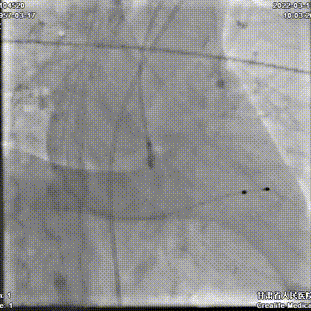

术中剪影:

手术影像:

主动脉根部造影

瓣叶增厚,中度反流

TaurusAtlas 20mm球囊预扩

冠脉灌注良好,无腰征

第一次定位释放

第一次释放后位置尚可

静待5分钟后位置明显下滑

回收调整超硬导丝后,再次定位

逐步释放瓣膜,工作位位置理想

工作位造影

瓣膜充分膨胀,完全释放

植入后位置理想,无反流